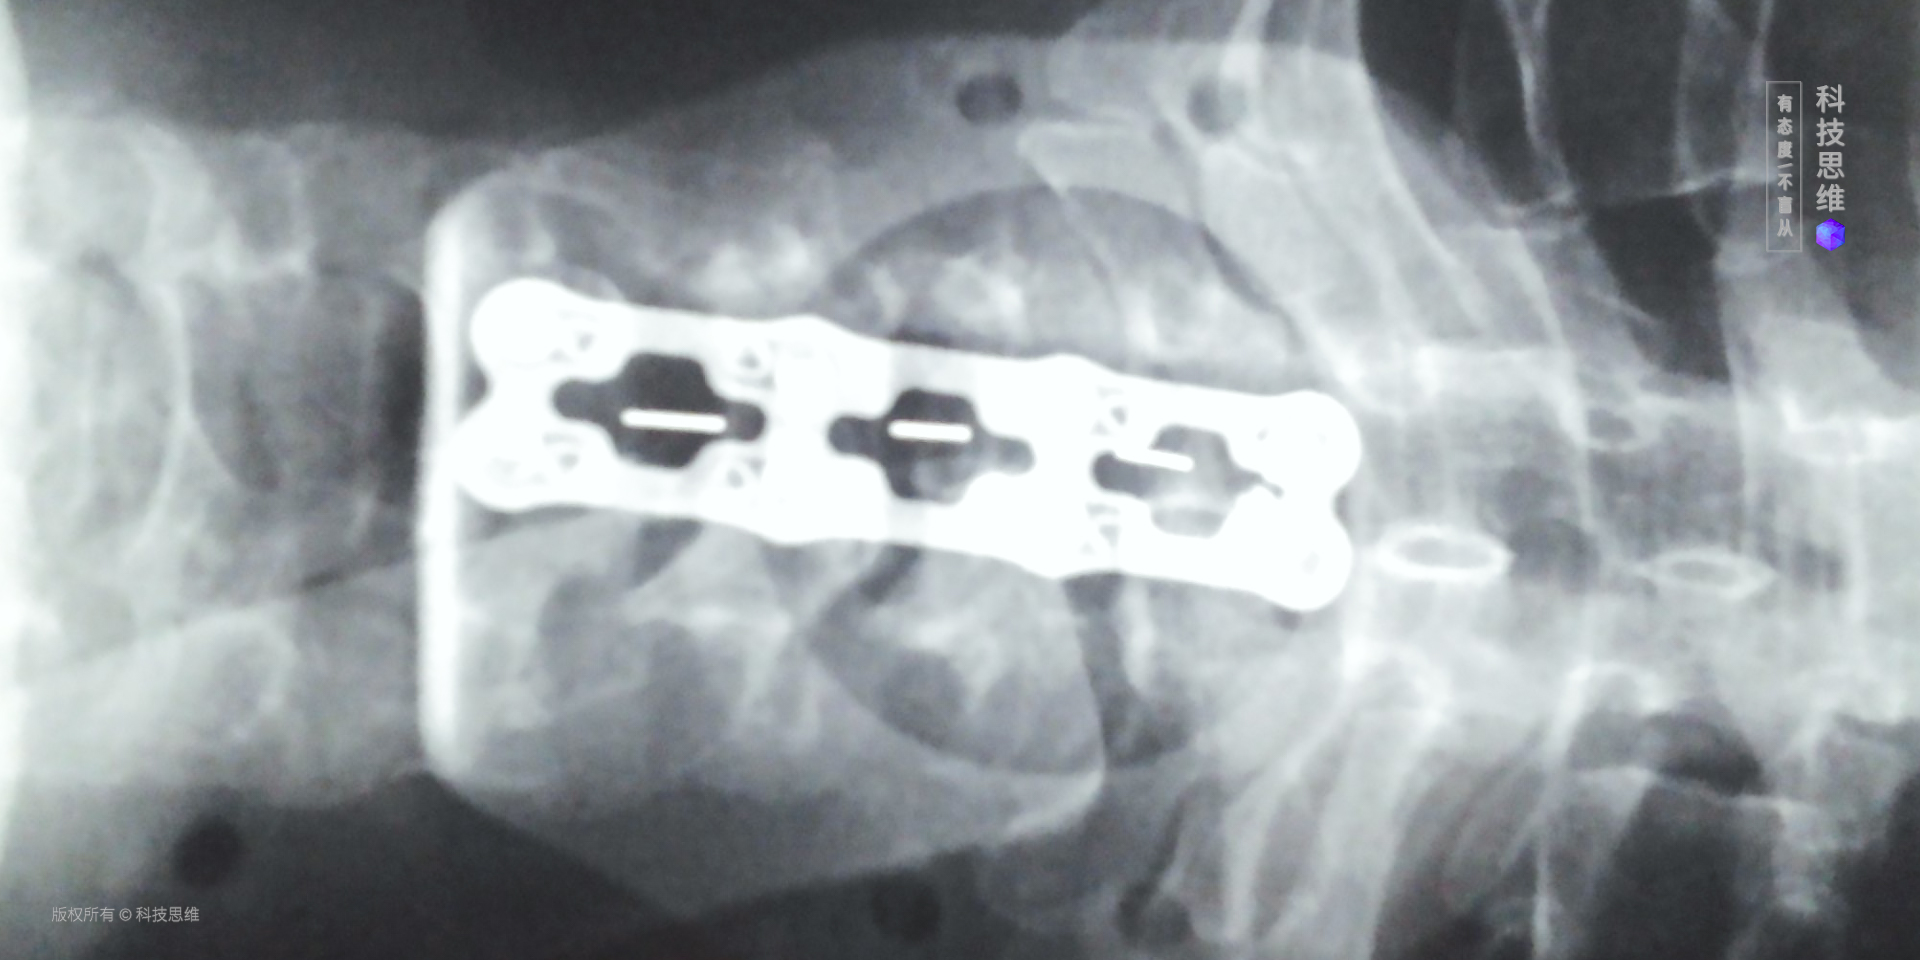

严重的都需要手术上钢板

还好,医生说我还不算太重,严重的都需要手术上钢板呢!只要配合治疗和锻炼,就能够缓解目前的病情。医生还很贴心的问了我的办公情况,告诉我,尽快更换一把符合人体工学的椅子,同时增高显示器的高度,尽可能减少脑袋前倾的情况。